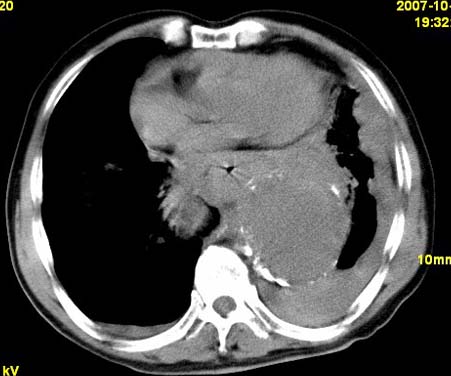

标题: CT10190:男,70,胸部疼痛数年,加重一天。典型病例。 [打印本页]

标题: CT10190:男,70,胸部疼痛数年,加重一天。典型病例。

典型降主动脉瘤伴血栓形成.瘤体下部局部边缘不清,结合病史,不除外局部撕裂外渗可能.另左侧胸水,肺部压迫不张改变.建议增强进一步检查.

典型降主动脉瘤伴血栓形成。支持:降主动脉瘤!

考虑胸主动脉瘤并血栓形成,胸腔积液

1.降主动脉瘤伴血栓形成.2.左侧胸腔积液,考虑为主动脉瘤破裂所致。

降主动脉明显增粗,边缘模糊,周围低密度影,双侧胸膜腔少量积液,结合临床考虑胸主动脉瘤破裂并双侧胸腔积液。